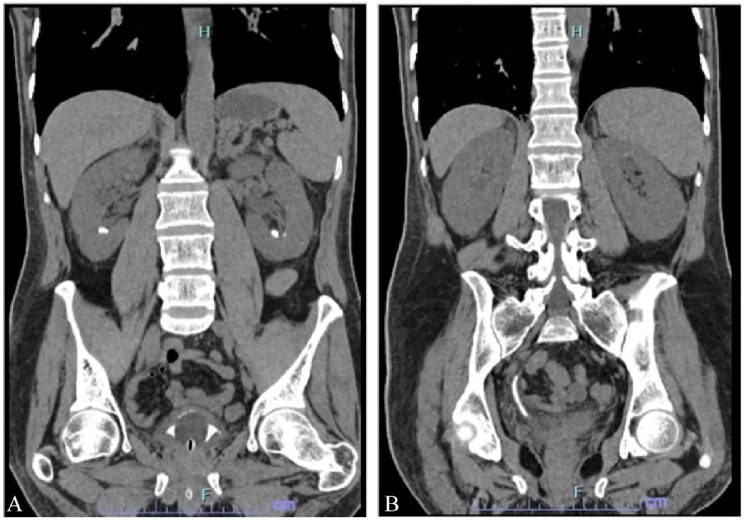

Fungal bezoar formation is a complication of fungal urinary tract infections that are usually caused by Candida species and other fungal types. They can form in any site along the urinary tract and may cause an obstruction to the urine flow that would require drainage by nephrostomy, a ureteric stent, and sometimes surgical intervention is needed. In this case report we discuss a case of an adult male who had an extensive fungal bezoar infection caused by Candida tropicalis causing him anuria and acute kidney injury. The bezoars were found in the bladder, the ureters, and both kidneys. The patient was treated with bilateral ureteric stent insertion and with fluconazole for 3 weeks. Bilateral ureteroscopy and urine culture were done after 2 months and they showed that the bezoars have been eradicated on both gross and microscopic levels.